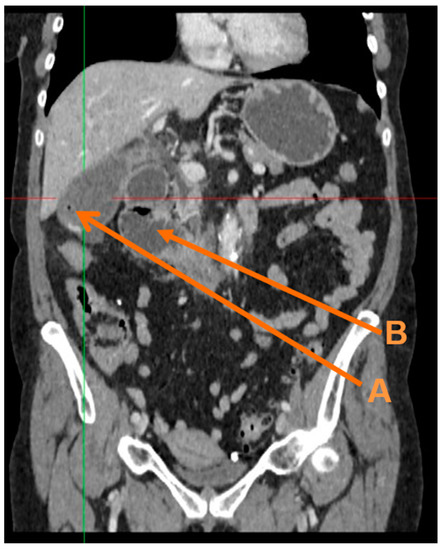

The thick-walled gallbladder, containing sludge, air and stones remained unchanged (Figure 1). No intra- or extra-hepatic bile duct dilatation was observed. The first and second part of the duodenum was distended (Figure 1) and fluid-filled with an apparent transition point in the third part.

Figure 1.

Coronal computerised tomography (CT) reconstruction showing: (A) Gas in the gallbladder, and (B) localised duodenal ileus.